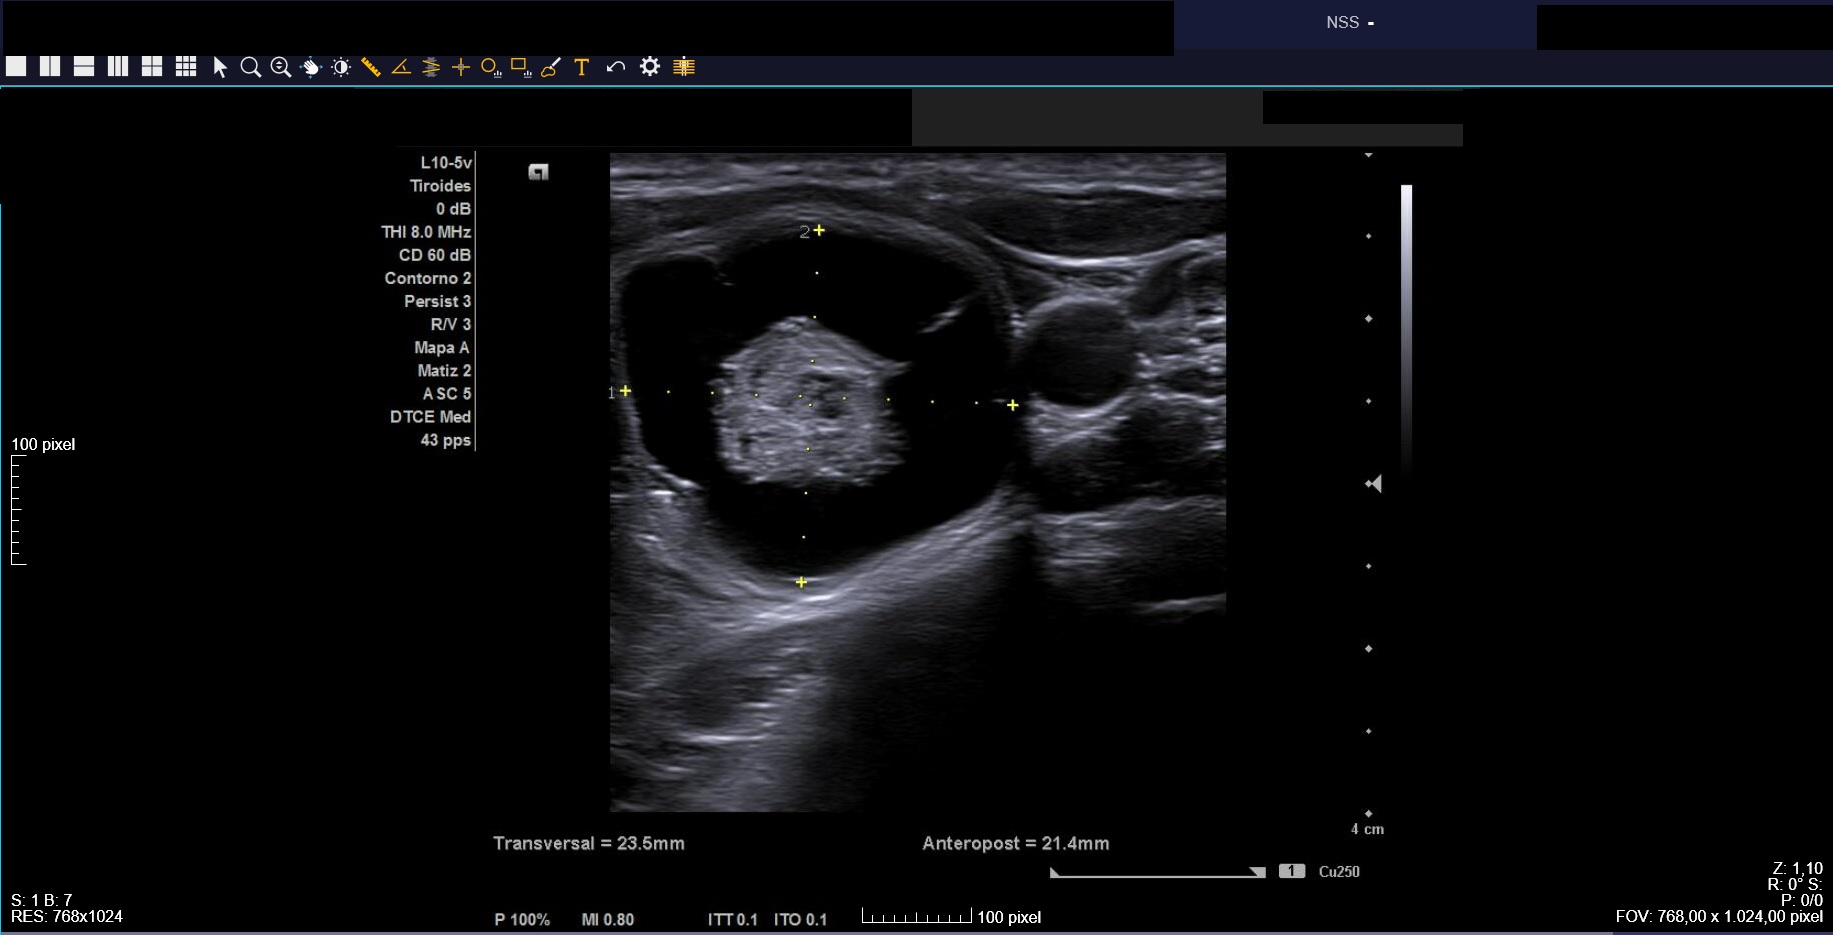

Ecografía clínica: tiroides de tamaño normal con ecoestructura homogénea. En lóbulo tiroideo izquierdo nódulo de 3 cm, anecoico, márgenes bien definidos con imagen hiperecoica en su interior (Imágenes 1, 2 y 3).